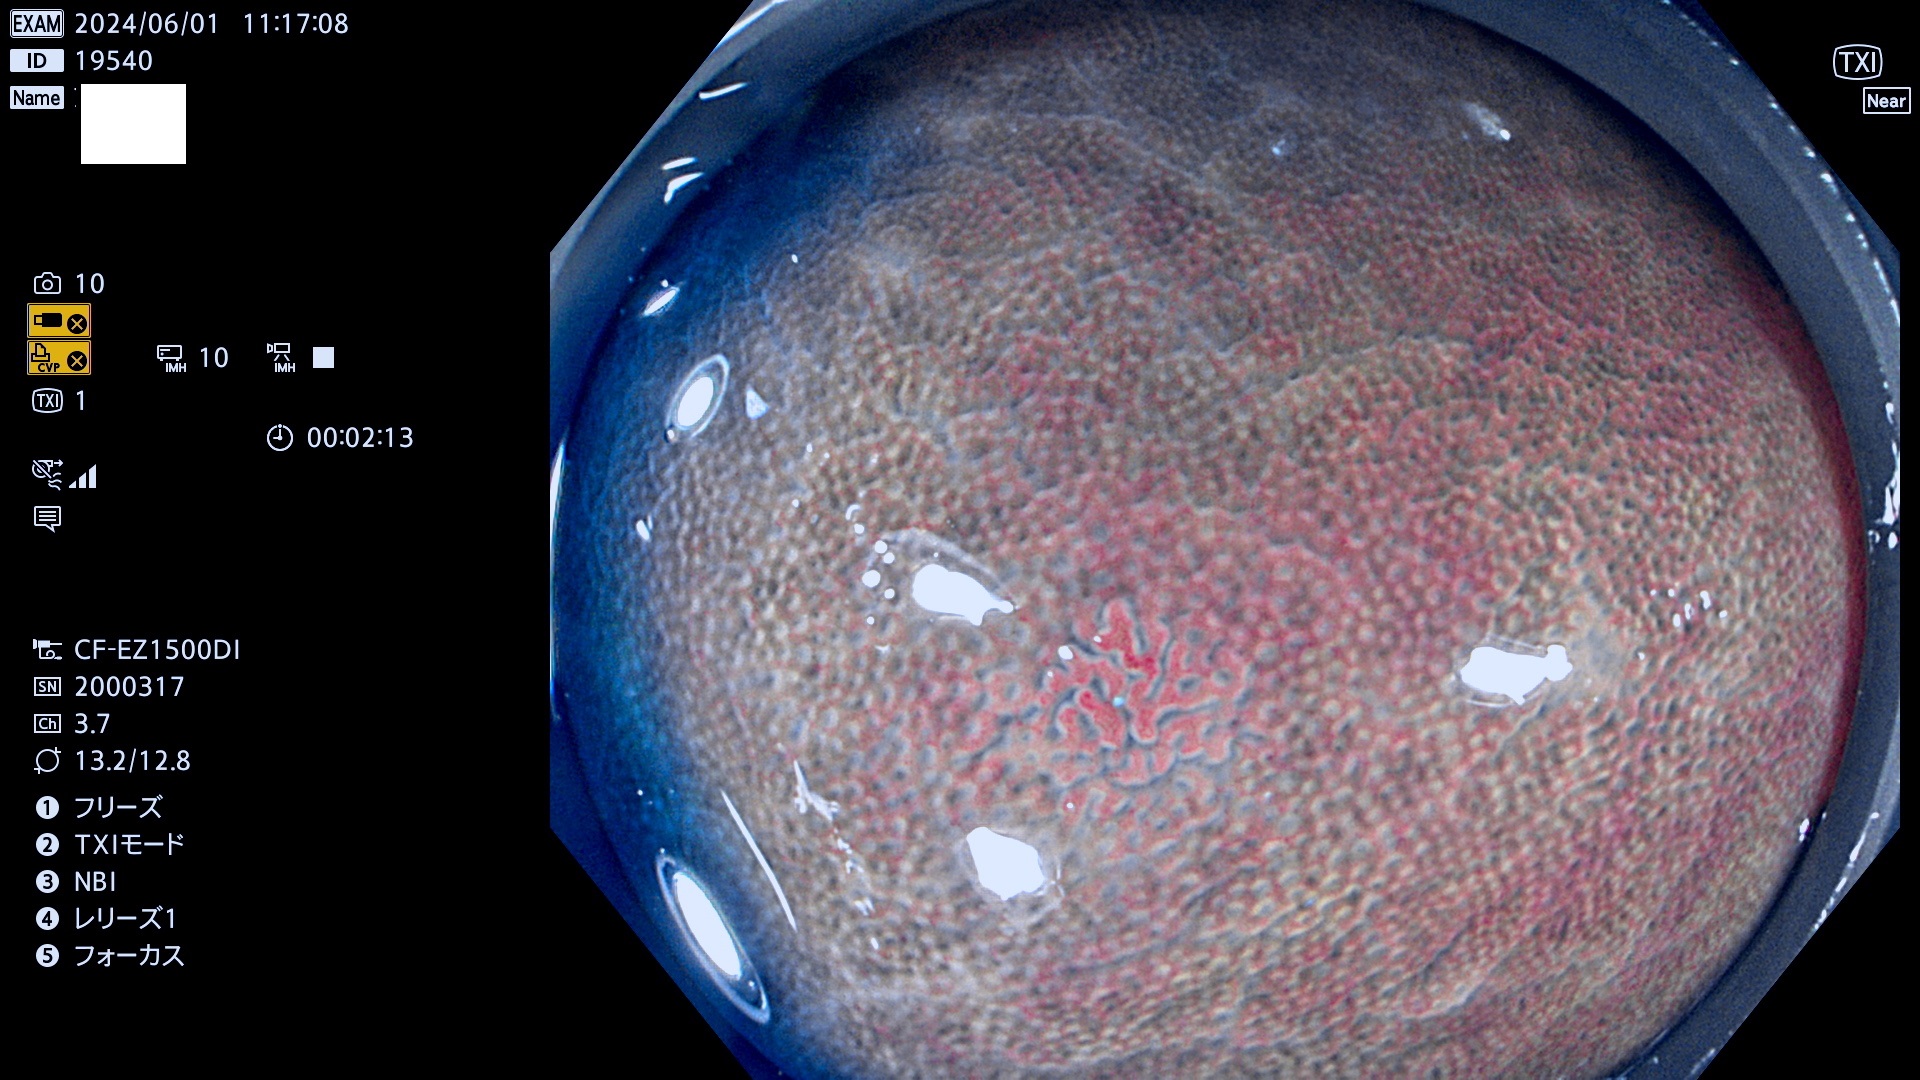

今週のUb、Uc型腺腫

表面型腺腫(Flat Adenoma)の中で、完全に平坦な物をUb、陥凹している物をUcと呼びます。平坦隆起型(Ua)よりも、発見が難しく危険な病変です。

毎週の検査(木・金・土・日)に発見されたUb、Uc型・腺腫を、その週の日曜の夜にUPし1週間、提示します。

抽出の対象期間 2024年5月30日〜6月2の4日間(40件の検査)7件 (7/40=18%)